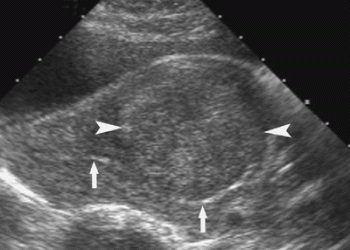

Το υπερηχογράφημα αναδεικνύει διάφορες γυναικολογικές παθήσεις, όπως ινομυώματα της μήτρας, κύστεις των ωοθηκών, υπερπλασία του ενδομητρίου, πολύποδες, κλπ. Μπορεί επίσης να χρησιμοποιηθεί για την παρακολούθηση της ωρίμανσης των ωοθυλακίων σε γυναίκες με υπογονιμότητα, ή σε γυναίκες που λαμβάνουν αγωγή για την πρόκληση ωορρηξίας.

Ινομύωμα Μήτρας

Κύστη Ωοθήκης